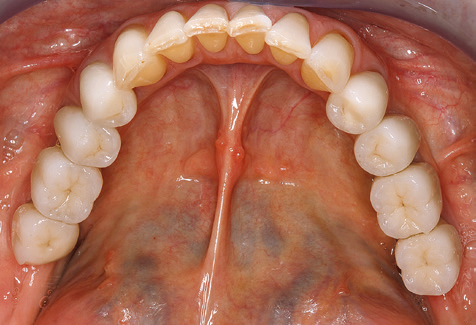

A 52-year-old patient presented in our clinic for the first time in 2004 following tooth loss in the third quadrant, expressing a desire for a new prosthetic restoration. Periodontal and radiological diagnostics revealed the need for extensive periodontological treatment. In addition, teeth 48, 28 and 27 were attributed a very poor prognosis and were subsequently extracted (Fig. 1). Following the successfully completed, systematic periodontological treatment, a fixed dental implant was inserted with the introduction of five implants in tooth regions 35, 36, 37, 46 and 47. Prosthetic treatment of the natural teeth was effected with veneered zirconium dioxide ceramic crowns; the implants were composed of two-piece, individual zirconium dioxide abutments and similarly veneered crowns made of a zirconium dioxide ceramic (Cercon base colored, Dentsply Sirona Lab). Definitive insertion of the prosthetic restoration occurred in 2005.

The ten-year check-up revealed no indications of advancing clinical attachment loss or peri-implant bone substance loss (Fig. 3).

Standardised and regular risk-adapted care in the scope of SPT is the key to treatment success for the clinical long-term success in periodontically compromised patients. This is particularly true for patients fitted with implants following successfully completed periodontal treatment (Fig. 11a and b).